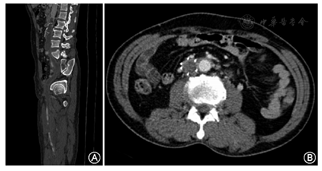

本研究中60例患者共780支血管接受CTV检查,326支血管有阳性发现(41.8%,326/780)。患者CTV征象主要为扩大的静脉管腔内局灶或多发中心性、偏心性或不规则充盈缺损,或呈条带状累及一支或多支血管,周围侧支循环形成。由于静脉回流受阻,患肢肌肉及皮下脂肪组织明显肿胀,故可见水肿增厚筋膜影(图1,图2)。

60例患者共420支血管行单侧下肢静脉DSA诊疗,332支血管有阳性发现(79.0%,332/420)。患者DSA征象主要为单发或多发充盈缺损,部分血管管腔不显影,周围侧支循环形成。下肢静脉形成血栓的患者通过抬高患肢,增加对比剂总量增加下腔静脉显影度,小腿部还可加袖带,注射对比剂时触发测压,增加小腿压迫从而增加下腔静脉血流回流量。血栓分布情况及诊断结果对比分析分别见表1,表2。以DSA检查结果为金标准,低剂量CTV的灵敏度、特异度分别为96.2%、92.6%。低剂量CTV和DSA两种方法检查结果在kappa一致性检验中kappa值为0.860,P<0.05,说明两种方法对DVT诊断具有很好的一致性;在配对χ2检验,P=0.263,两种检查方法差异无统计学意义。患者辐射剂量均值(225±44) mGy·cm。均显示低剂量CT下肢静脉造影对DVT的诊断有很高的准确性(图3)。